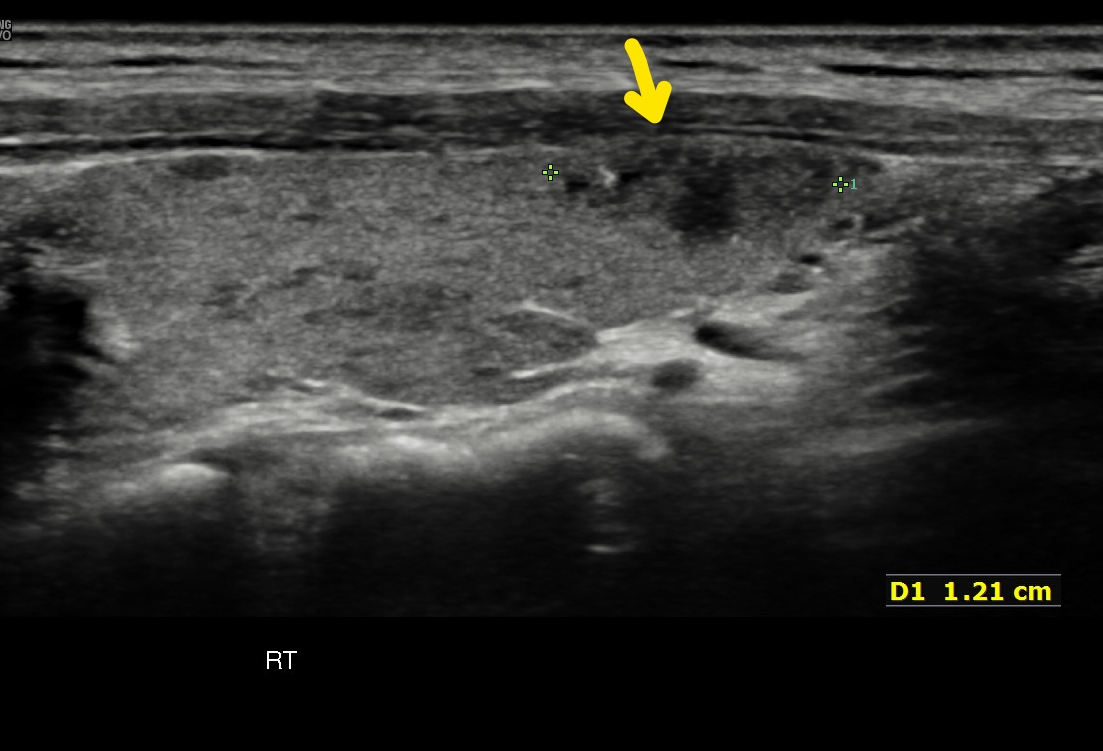

공주맨의 갑상선 우엽에 자리잡은 암덩어리